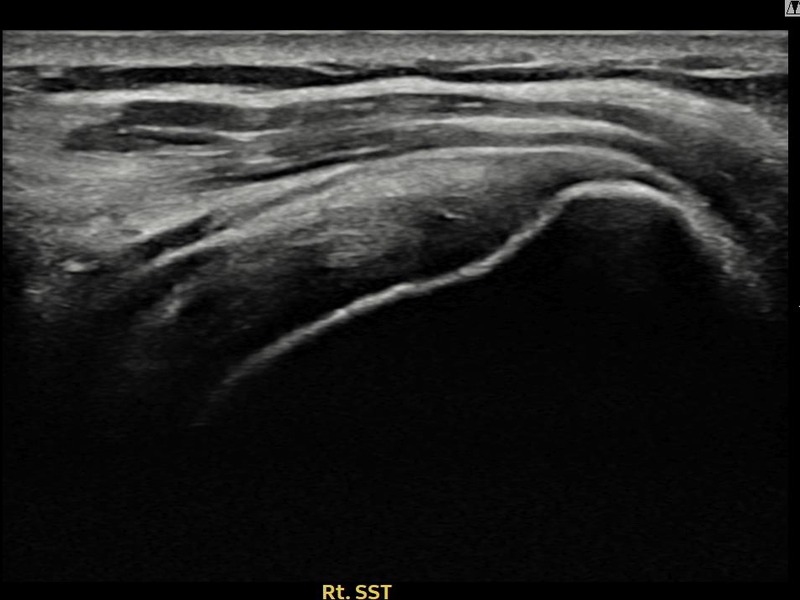

최ㅇㅇ님 · 우측 극상근건 관절면측 파열 진행형

우측 어깨 파열이 진행된 상태로 수술 없이 치료를 원해 내원하셨습니다. 다각도 초음파 평가 후 축소봉합술을 시행하여 힘줄 구조가 안정화되었습니다.

상세 보기 →